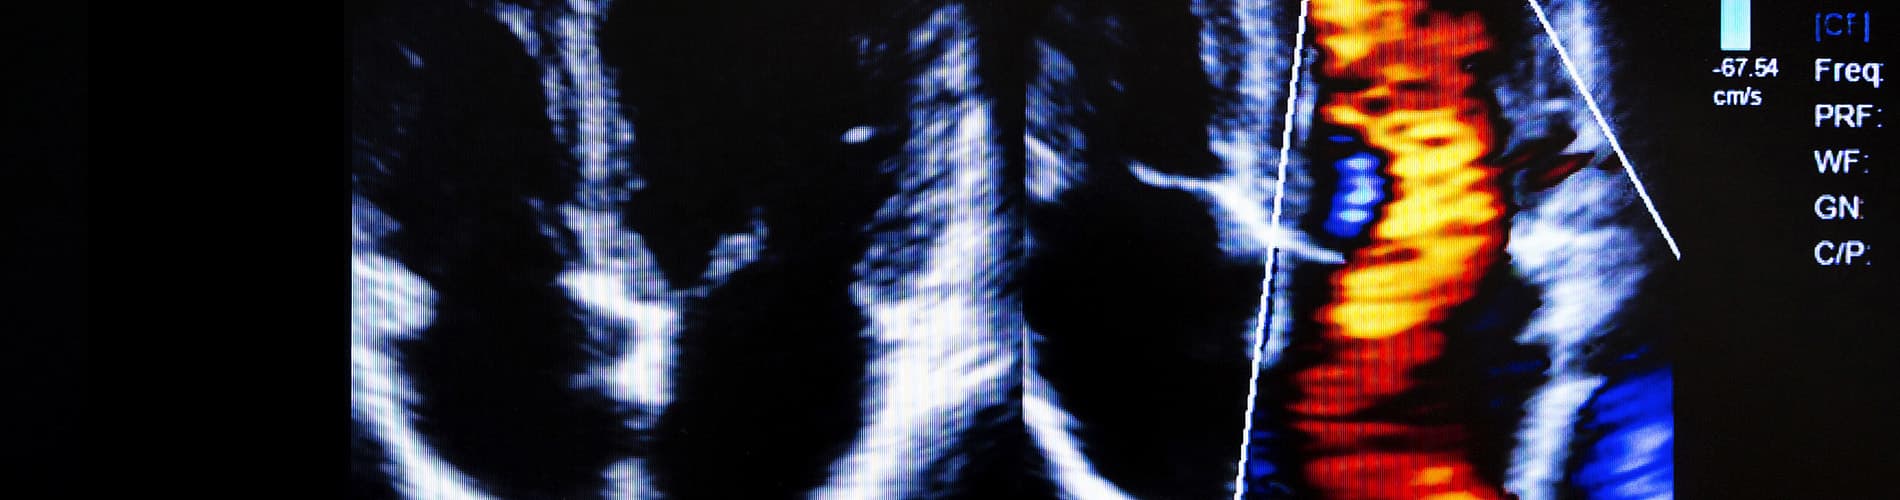

- Do you need an LA:Ao ratio to tell you which dog’s left atrium is dilated in the videos below?

There is a lot of pressure to obtain measurements from echocardiograms, particularly an LA:Ao ratio (the ratio between the diameter of the aorta and the diameter of the left atrium, usually taken from the short-axis 2D image) in canine and feline patients and wall thickness in felines – two of the most difficult measurements to perform well!

Reporting measurements before you are confident with your imaging is inadvisable: firstly, because your measurements will have poor reproducibility and may be inaccurate; and secondly, because you need to train your own interpretation skills. Relying on measurements when you first start can absolve you from having to interpret the image yourself and can easily give false reassurance.